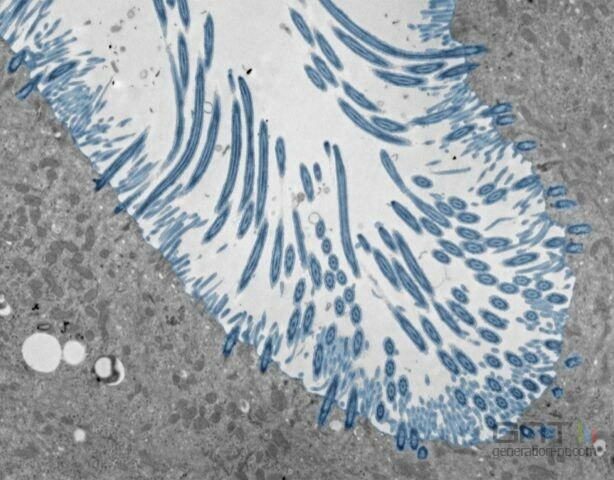

Pour comprendre cette variabilité, des scientifiques ont recréé un "nez en boîte". Ils ont cultivé des cellules souches nasales pour former des organoïdes, des versions miniatures de l'interface entre notre nez et l'air. Ces modèles complexes, dotés de cils vibratiles et de cellules productrices de mucus, ont ensuite été infectés par un rhinovirus. L'observation de milliers de cellules a permis de décortiquer la chorégraphie de la réponse immunitaire.

cellules nasales

Un organoïde nasal est une version miniature et fonctionnelle de la paroi interne du nez, cultivée en laboratoire à partir de cellules souches. Il permet aux scientifiques d'étudier comment les virus, comme le rhinovirus, interagissent avec les cellules humaines dans un environnement contrôlé, ce qui est impossible à faire sur des animaux qui ne sont pas sensibles à ce virus.